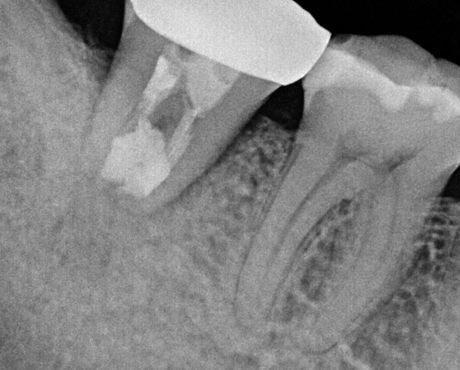

치료 전

의도적 발치 직후 뿌리 끝 염증 관찰

치료 1년 반 후